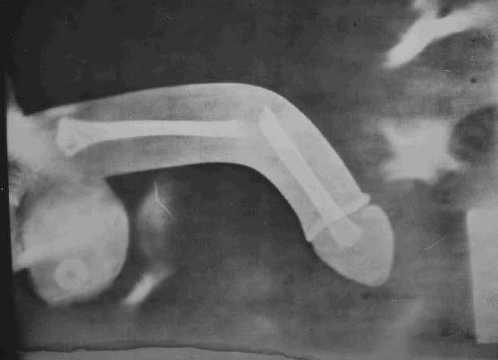

с перилы упал

Название изображения: с перилы упал

Ты после такгого ренгена бесплодным станешь!